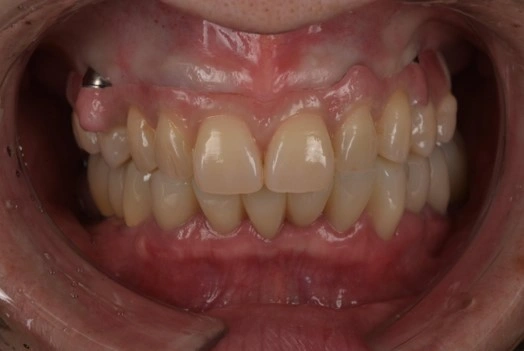

親知らず抜歯 症例①

親知らず抜歯 症例

治療例

親知らず抜歯 症例②

親知らず抜歯 症例③

費用例

総額 66,000円(税込)

年齢

20代女性

主訴

矯正治療のため、親知らずを抜きたい

治療期間

1時間半

施術(治療)内容

親知らず3本抜歯、腫れを軽減するためにCGFを行う

リスク・副作用

腫れる恐れがある、費用が高い

麻酔費用

22,000円×1回=22,000円

治療費用

抜歯代33,000円+CGF代(オプション)11,000円

親知らず3本抜歯、腫れを軽減するためにCGF(再生療法)を行う